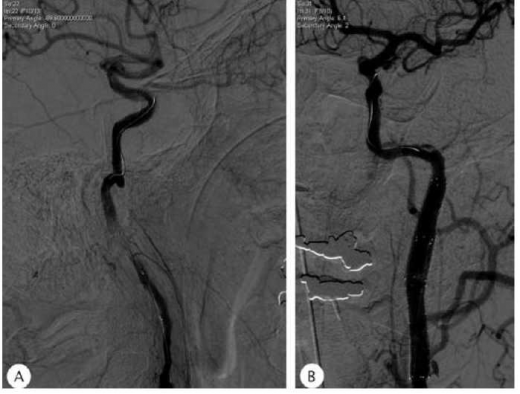

אפשרות טיפולית נוספת, השמורה למקרים נבחרים, היא צנתור והנחת תומכן (Stent). אפשרות זו טובה בעיקר לטיפול בחולים בהם יש חסימה של עורק פרוקסימלי בשלב החריף, או במקרים בהם הדיסקציה גורמת לתסמינים המודינמיים או המשך אמבוליזציה גם בהינתן טיפול תרופתי נאות. בספרות מתואר מקרה רפואי בו צנתור מסוג זה בוצע למעלה מ-12 שעות לאחר השבץ עקב חוסר יציבות על רקע המודינמי (תמונה 2).